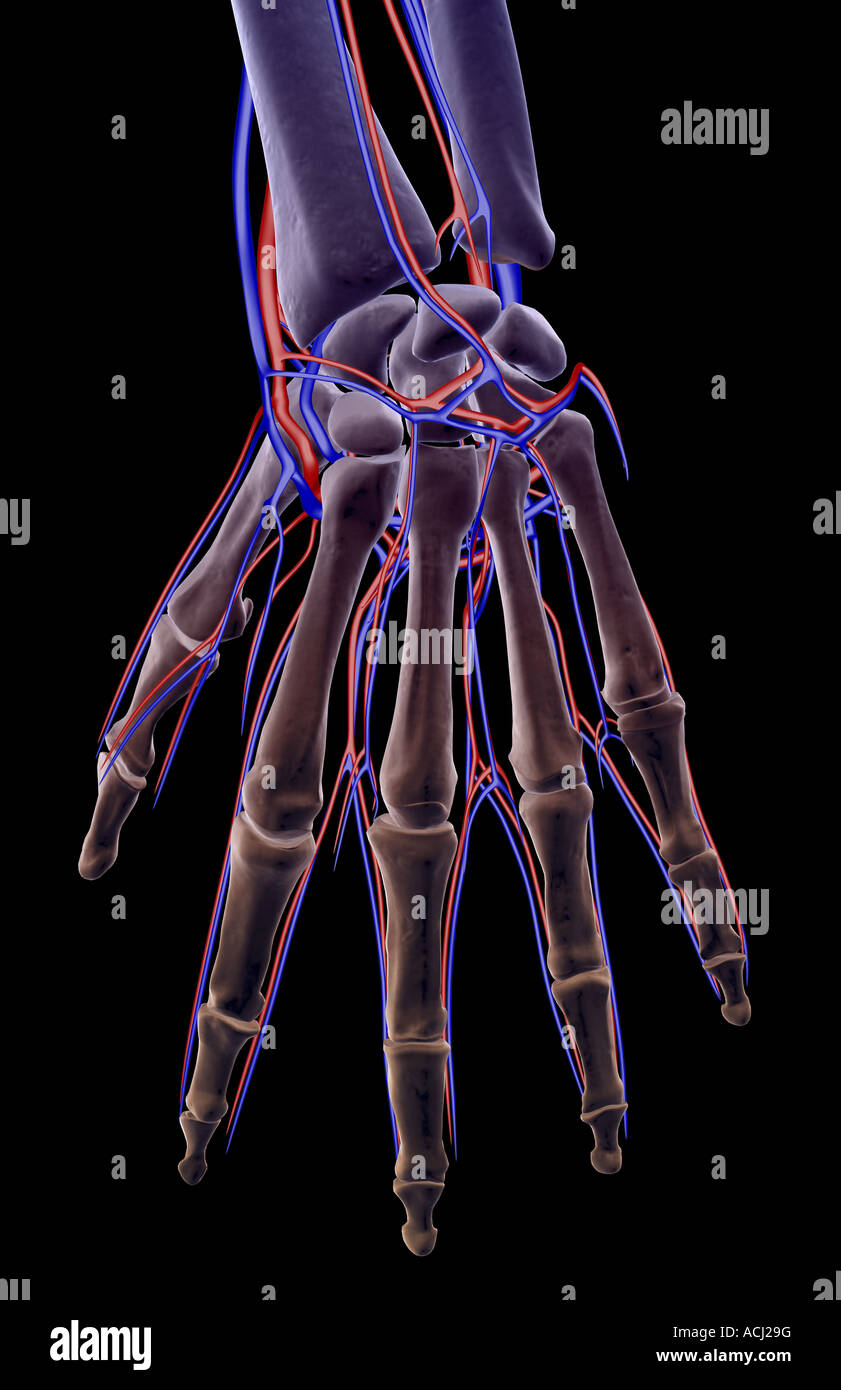

The blood supply of the hand Stock Photohttps://www.alamy.com/image-license-details/?v=1https://www.alamy.com/stock-photo-the-blood-supply-of-the-hand-13165707.html

The blood supply of the hand Stock Photohttps://www.alamy.com/image-license-details/?v=1https://www.alamy.com/stock-photo-the-blood-supply-of-the-hand-13165707.htmlRFACJ29G–The blood supply of the hand